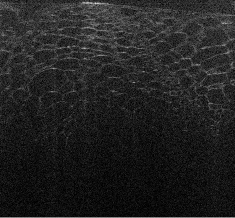

Visualizations of cross sectional reconstructions from the sub-sampled measurements are shown in Figure 2 and Figure 3 for the beaded gel and cucumber tissue samples respectively. Quantitative results of the NCC are then shown in Table 1.

From Figure 2, it appears that enhancement of the image structure is improved in each instance of MBIR. Random sub-sampling results in the best preservation of structure, followed by equispaced, and finally partial, which exhibits strong artifacts in each case. TV regularization appears to reasonably robust, but exhibits some block-like image artifacts, whilst DT-CWT has better preservation of speckle structure.

The cucumber tissues results in Figure 3 follow a similar trend to the beaded phantom, with very good preservation of structure for random and equispaced sub-sampling for both MBIR techniques. Again, partial measurements are significantly worse, with most of the structure degraded in the interpolated ISAM image.